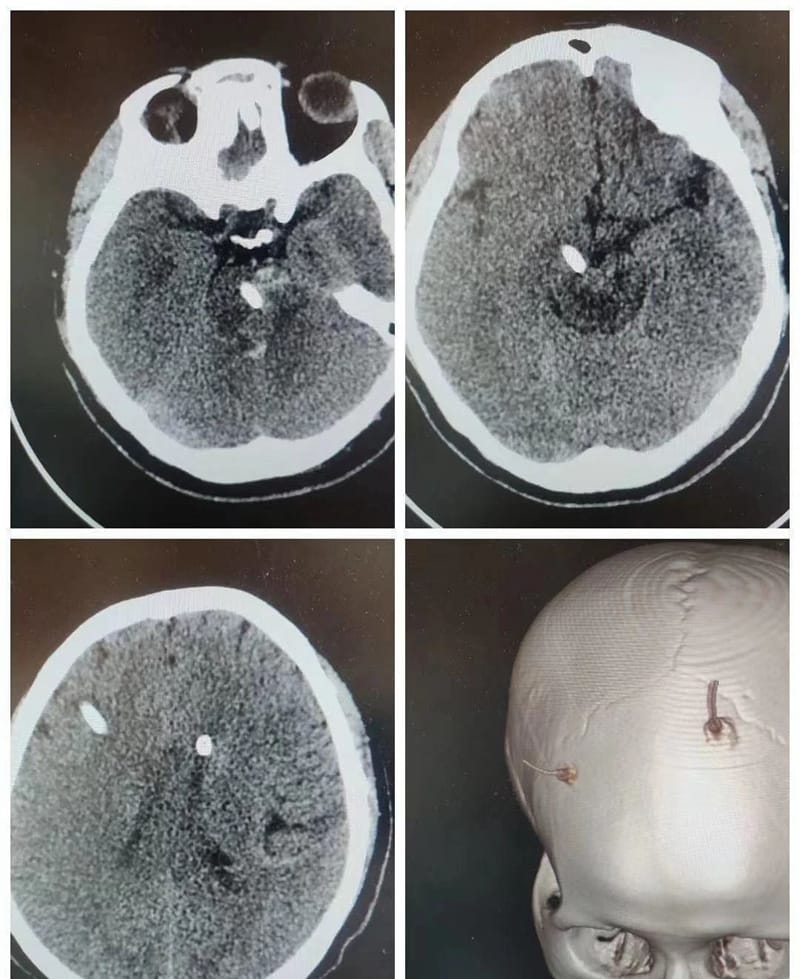

术后12小时患者恢复自主呼吸,生命体征平稳,复查头颅CT显示:脑干血肿已清除,原血肿区脑干水肿不明显,脑室引流良好。目前患者病情平稳,意识明显好转,四肢肌力也显著恢复。